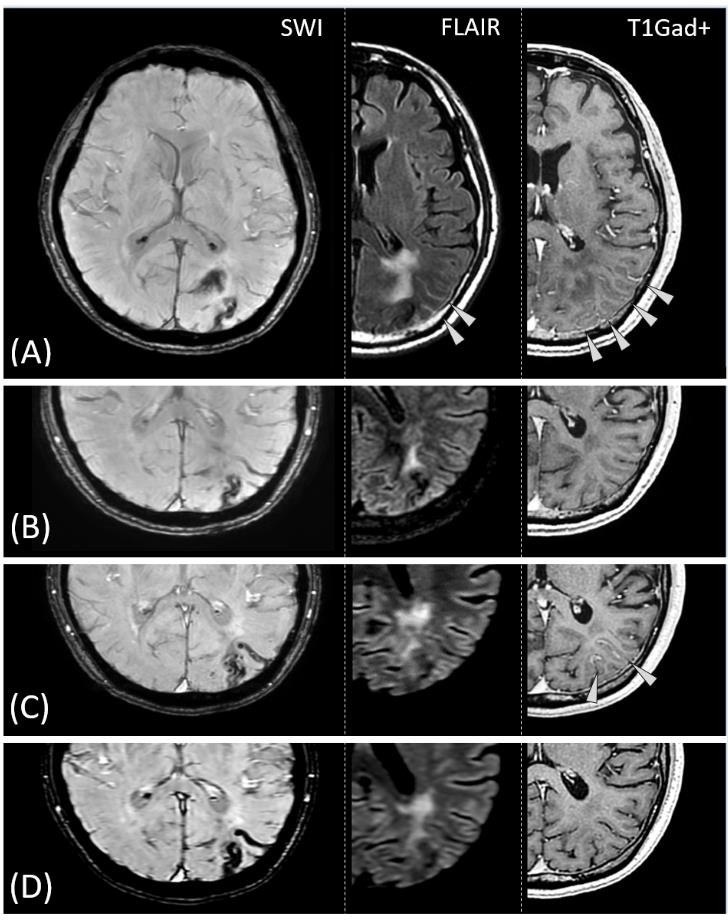

1. ábra. Az első diagnosztizált CAA és egyben CAA-RI beteg koponya képalkotó vizsgálatai. (A) Az évekkel korábbi agyállományi lebenyi vérzés maradványa. (B) A behozott friss CT vizsgálaton két apró hiperdenz (fehér) agyfelszíni vérzés; a korábbi vérzés helye körül kiterjedt ödéma. C) A koponya MRI vérzésekre érzékeny szekvenciáján számtalan különböző korú agyfelszíni vérlerakódás (jelszegény vagyis

„fekete” szalagok), lebenyi mikrovérzések (jelszegény pöttyök) és makrovérzések (jelszegény szélű nagyobb állományi eltérések), a mély agyterületek érintettsége nélkül, CAA-ra jellegzetes módon. (D) Összefolyó aszimmetrikus T2 jelintenzív (világos) ödémás eltérések, melyek gyulladásos CAA-ra (CAA-RI) jellegzetesek.

Szalardy et al. 2024, Neuropathology and Applied Neurobiology nyomán.